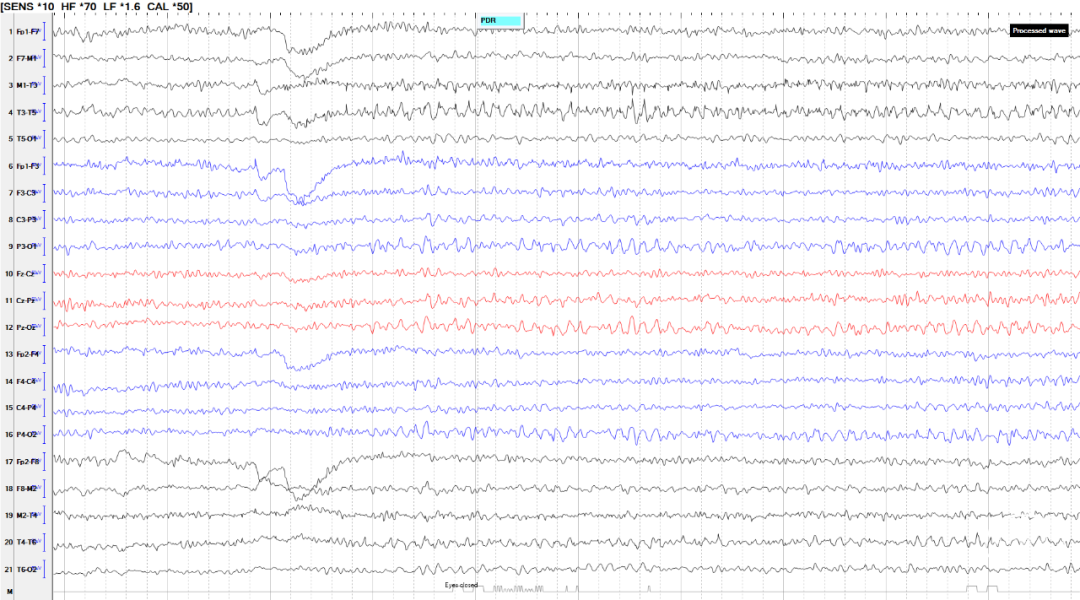

患者于5月龄首发,诱因:发热1周,热峰40℃,表现为发热第1天出现双眼上翻,无肢体抽搐,持续数分钟;15月龄学步后发现行走易跌倒,坐位时出现头颈及躯干向一侧倾斜,每次持续2-3秒,每天发作数次,声音刺激可诱发;病程中仅17岁出现1次全身僵直抖动;23岁后发作较前稍有缓解,声音刺激无发作,平均1-3次/天,表现为:发作性肢体僵直,每次持续2-3秒;患者幼年起病,辗转多家医院仍发作频繁,反复跌倒至头面部频繁外伤。后转求我院,完善脑电图检查提示清醒期背景活动正常(图1),间歇期放电,弥漫性,中线-右旁中线著(图2-3),2天共监测到30次临床发作,表现为强直发作,累及颈肌、躯干、四肢,以左侧肢体为著;同步脑电图示弥漫性低波幅快节律,以中线-右侧旁中线为著(图4-5)。头颅MRI可见双侧岛叶、基底节、枕叶异常信号(图6)。头颅PET见提示多发低代谢区(图7)。

图1.清醒期背景活动正常